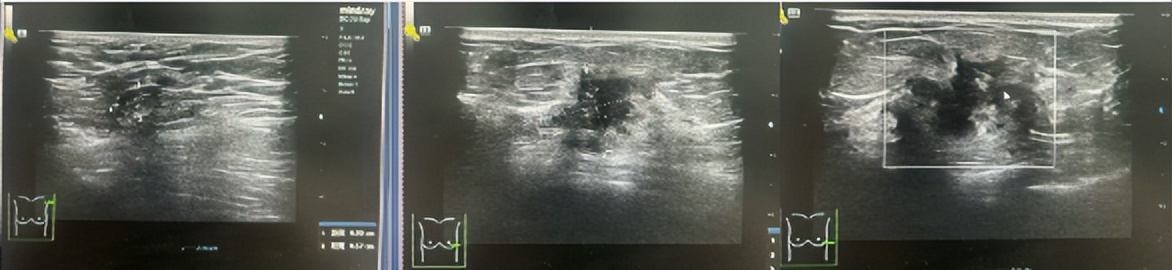

·乳腺彩超

2023-06-26彩色多普勒超声宽景成像+术前体表定位:

1、左乳4点钟方向实性肿块(乳腺Ca可能,BI-RADS 4C类),已体表定位,此次定位仅供手术医生参考。

2、双乳乳腺增生症。

3、双侧腋窝探及多个淋巴结。

图1.2023年6月24日乳腺彩超